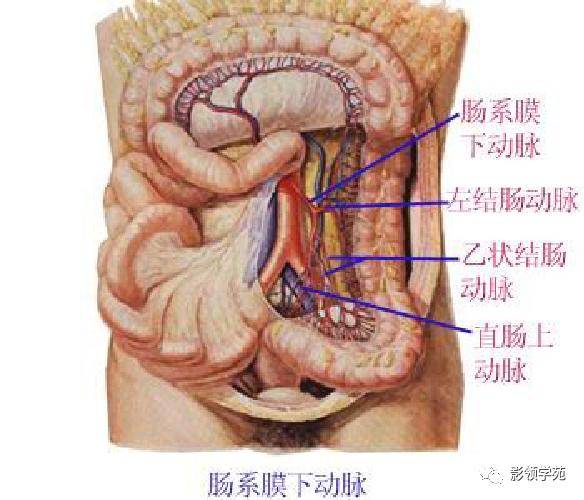

腹部动静脉

腹部动静脉